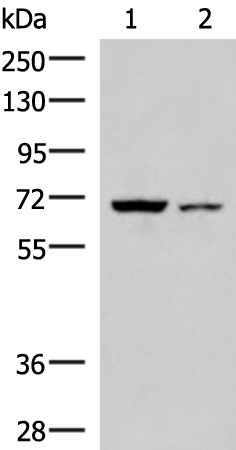

分类: 科研抗体货号: P10135别名: GRAB应用: WB反应种属: Human, Mouse, Rat